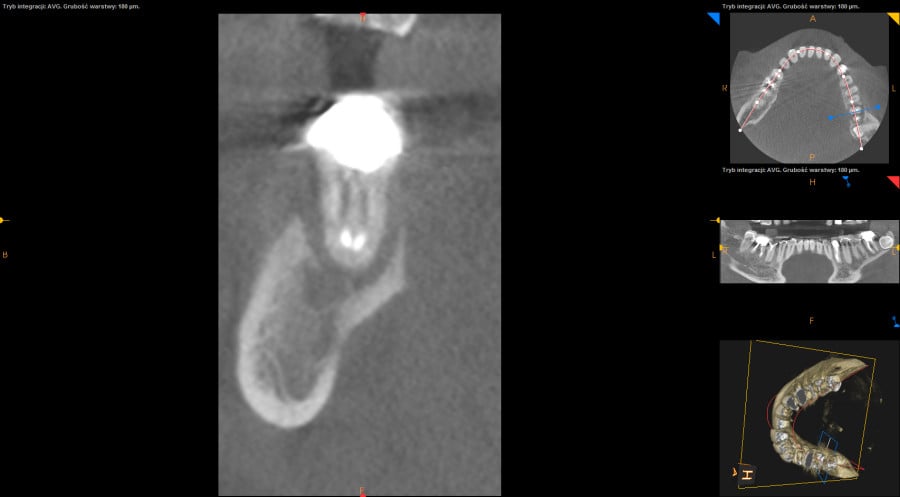

Ten problem najczęściej dotyczy zębów trzonowych żuchwy oraz górnych przedtrzonowców. Może również towarzyszyć wadom zgryzu, w zębach zniszczonych przez erozję, abrazję lub atrycję. Pionowe złamanie korzenia jest trudne do zdiagnozowania. Zdjęcia RTG nie zawsze bowiem ukaże „całą prawdę”. Coraz powszechniej używane obrazowanie CBCT (3D) pomaga w postawieniu diagnozy pionowego złamania zęba lub korzenia.

Do pionowego złamania korzenia zęba może dojść podczas zabiegu leczenia kanałowego poprzez używanie zbyt dużej siły w czasie wypełniania lub oczyszczania kanału. Może być również spowodowane zaklinowaniem się narzędzia w kanale. Pionowe korzenia zęba zawsze prowadzi do usunięcia całego zęba. Dbałość o profilaktykę i terminowe zgłaszania się do gabinetu stomatologicznego z towarzyszącą diagnostyką rentgenowską znaczącą redukuje te ryzyka.